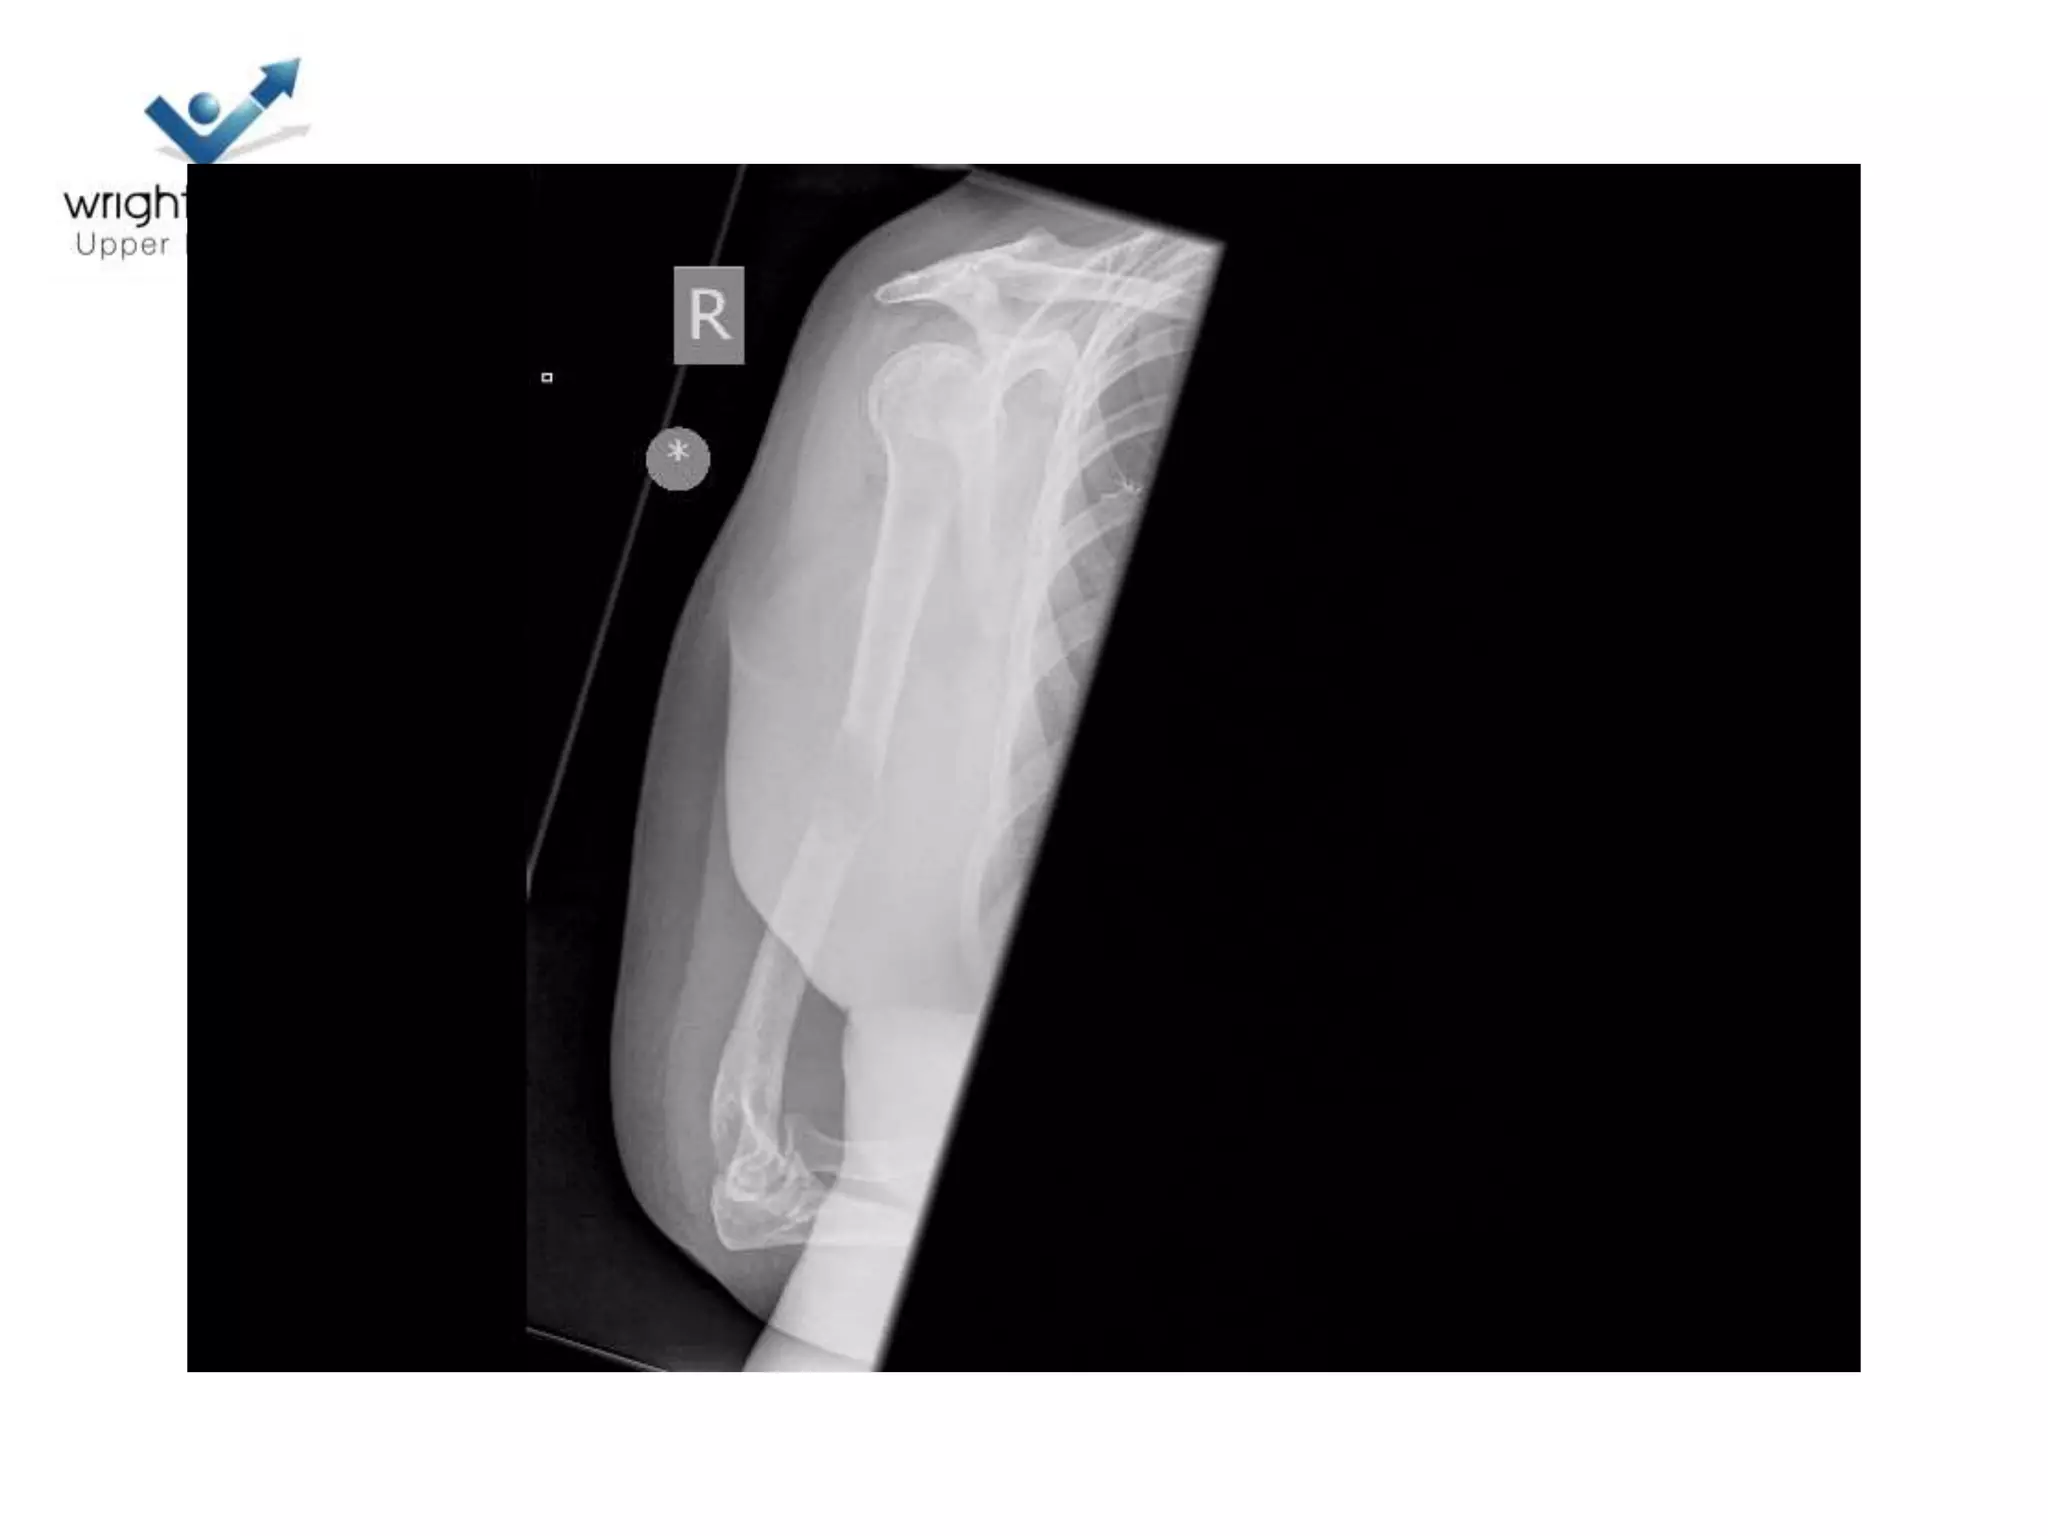

9 Next

10 Next